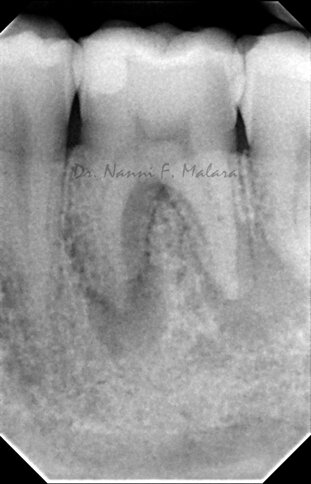

Molare affetto da lesione periapicale a carico di entrambe le radici (Alla radiografia si presentano come aree scure intorno alle radici)